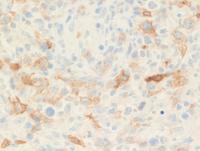

Immunostaining of Lymphoepithelioid variant (Lennert's lymphoma)

Scattered CD3+ neoplastic lymphoid cells are present. CD4 stains mostly the histiocytes while CD8 is expressed in the neoplastic cells. The neoplastic cells are also positive for TIA-1, a markers of immature cytotoxic phenotype which often correlates with CD8 expression. Rare CD30+ cells are present.